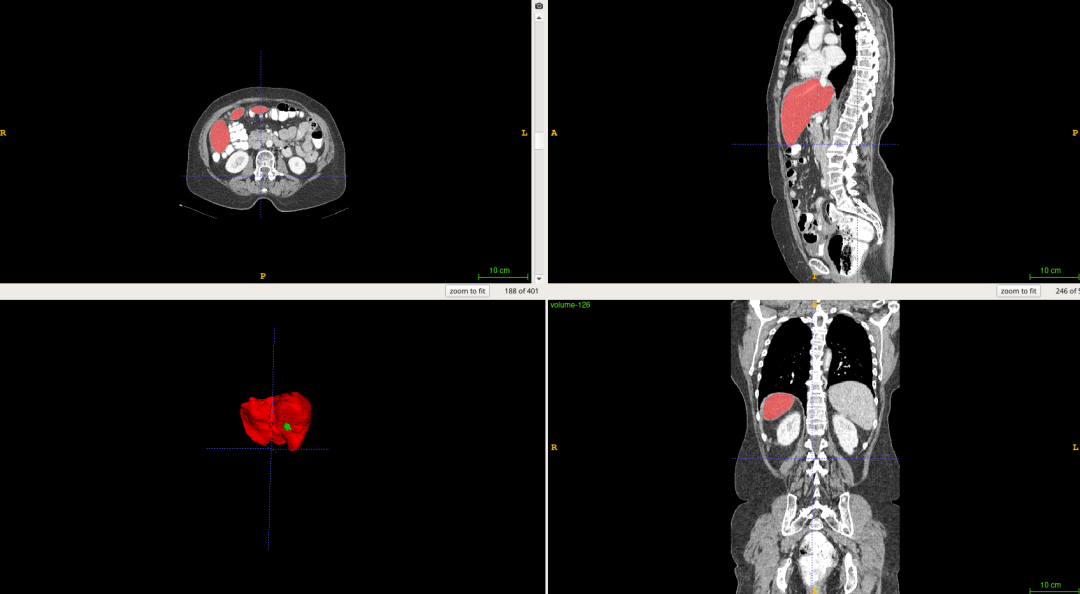

![]()

图6 分割结果

深度学习算法对一组CT扫描进行分割大概耗时15S,其效率明显高于医生阅片的效率。而且从分割结果中,我们可以计算获得肝脏体积,肿瘤数量,肿瘤体积,肝脏肿瘤负担等数量化的指标,更好地辅助医生进行诊断。